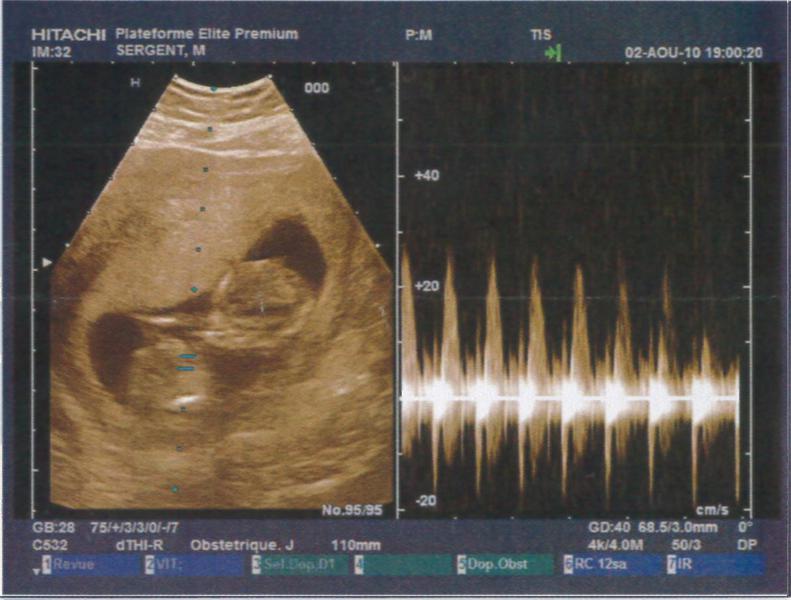

Je suis à 12SA soit 10SG, j'ai fait mon écho hier soir et tout va super bien !!! Je suis trop heureuse je vais vraiment pouvoir vivre ma grossesse à fond !! La nuque est parfaite, à vérifier par le test de la trisomie la semaine pro en même temps que la déclaration !!

Je vous met les photos des échos mais je trouve que l'on ne voit rien par rapport aux superbes images que nous avons vues !! Mais c'est pas grave, on a un super souvenir quand même !!

echo2.jpg

53.8 KB · Affichages: 68

• echo3.jpg